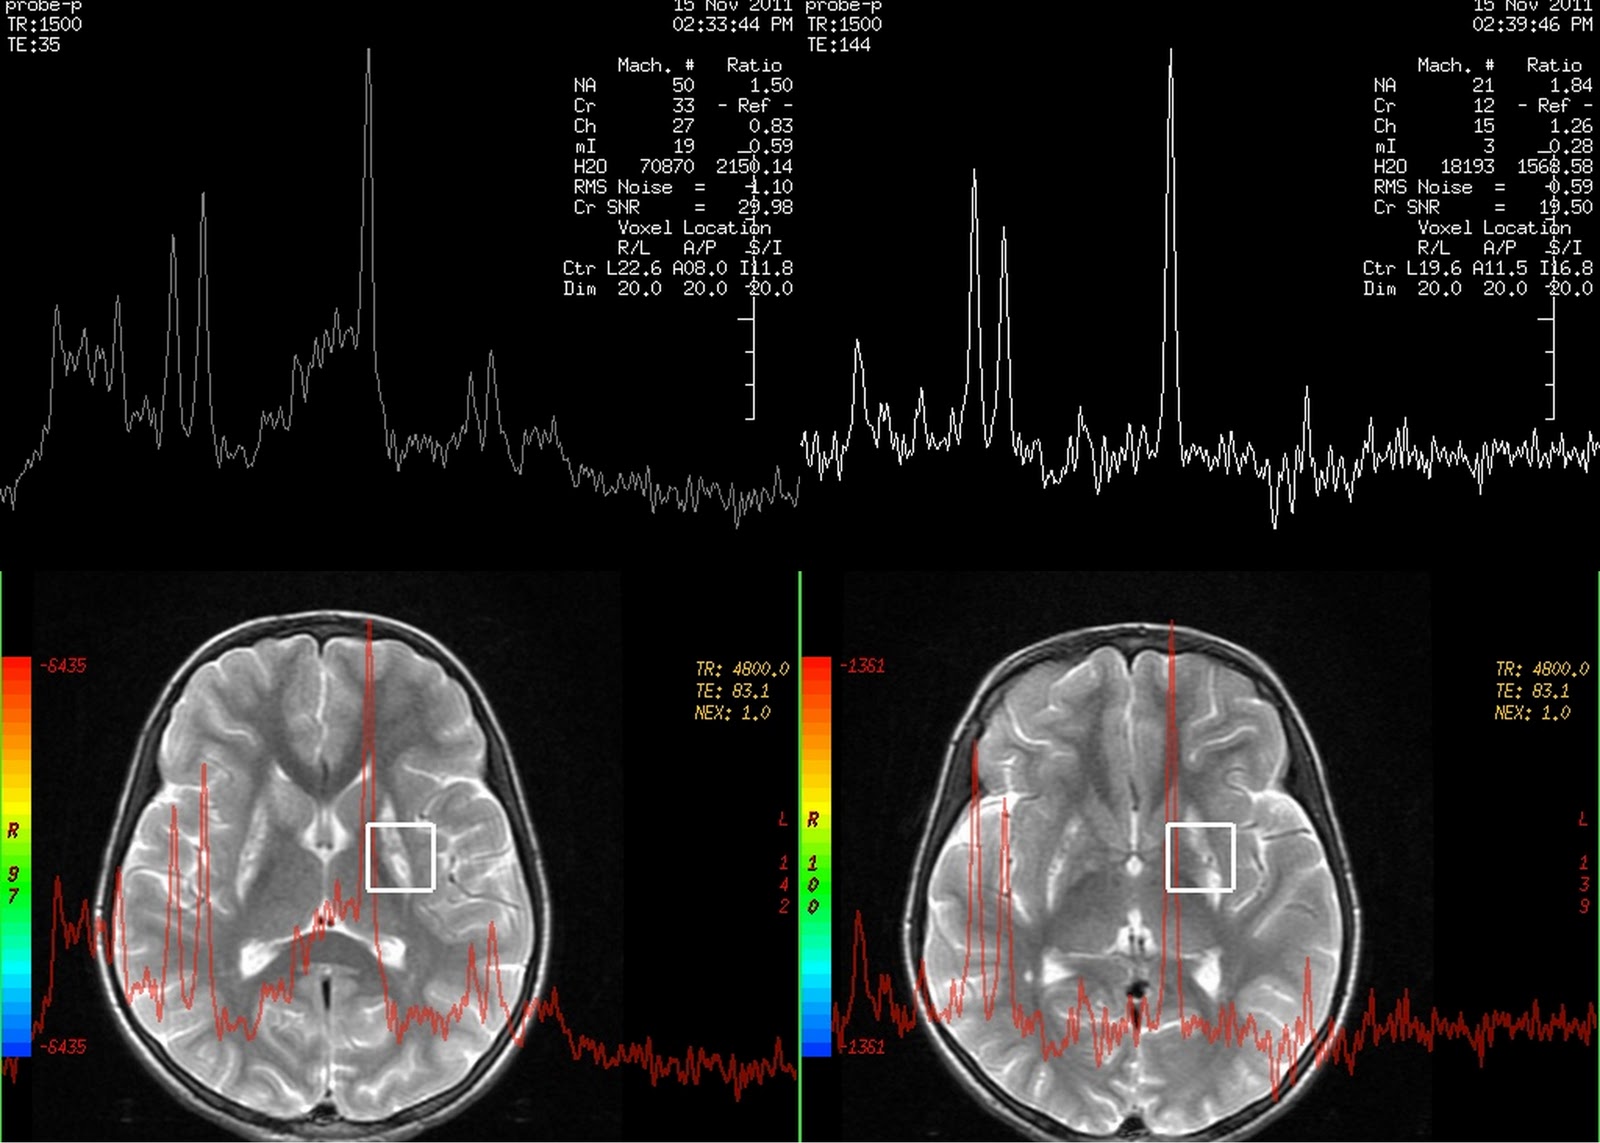

Dr Balaji Anvekar FRCR Leigh's MR Spectroscopy

MRI spectroscopy showing signal abnormalities with lipidlactate peak Spectroscopy Vs Mri Magnetic resonance spectroscopy (mrs) is a technique which can provide. Handout explains how an mri spectroscopy scan works, how it is done, how to prepare, what to expect, and how to get your results. While magnetic resonance imaging (mri) identifies the anatomical location of a tumor, mr spectroscopy compares the chemical. Magnetic resonance (mr) imaging, or simply mri, became the. Spectroscopy Vs Mri.